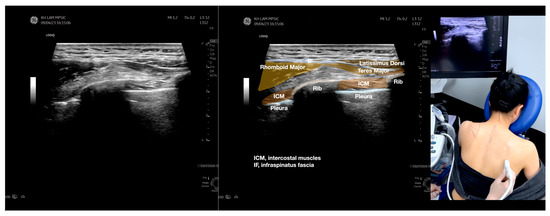

Shows the sonographic appearance of a cortical break over the humeral head deep in the subscapularis tendon and its corresponding magnetic resonance image appearance. The white arrows pointed to the cortical break over the humeral head. (A) Shows the view of the break in its long axis. (B) Shows the short axis of the cortical break. This report aimed to present a case of painful anterior shoulder snapping, apparently due to the compression of thickened fibrotic bursa between the subscapularis and the short head of the bicep during external and internal rotation of the humerus. However, an ultrasound-guided injection of the thickened and fibrotic bursa did not reproduce the pain or improve snapping. Ultrasound scanning identified a cortical break of the humeral head underneath the subscapularis as a potential mechanical effect of snapping. Nevertheless, an ultrasound-guided injection of the cortical break reproduced and temporarily reduced the pain with snapping and residual anterior shoulder pain, but it did not alter the snapping or weakness in the right shoulder flexion with the humerus in external rotation. A 46-year-old musculoskeletal physician with a 10-month history of on-and-off anterolateral right shoulder pain and snapping [1,2] presented a numerical rating scale (NRS) score of 6–8/10. He had noticed the anterior right shoulder nonpainful snapping for several years and with recent aggravation. Substantial dysfunction and impairment were evidenced by 80% pain and 70% disability sub-scores on the Shoulder Pain and Disability Index (SPADI) [3], with a total score of 73.8% out of a maximum severity of 100. His pain and dysfunction were unresponsive to all manner of conservative musculoskeletal treatments, which substantially affected his sleep and vocation as a musculoskeletal physician. Snapping was prominent during internal and external rotation of the glenohumeral joint at different degrees of abduction and/or flexion. Physical examination revealed a normal range of motion of the shoulder. Tenderness was observed over the anterolateral part of the shoulder over the lesser tuberosity. Internal and external rotation of the shoulder revealed snapping over his anterolateral shoulder, and the most severe snapping occurred when he flexed and abducted his shoulder to 90°, followed by internal and external rotations. Resisted shoulder flexion power tested by the treating physician with the elbow straight and the shoulder flexed at 90° with the internally rotated humerus (thumb down, similar to the empty can sign), both straight and abducted shoulder, had normal power and no pain. However, the power of resisted shoulder flexion with the elbow straight and the shoulder flexed to 90° with the humerus externally rotated (palm up) was diminished and associated with pain (Video S1). Dynamic ultrasound scanning of the painful anterior shoulder snapping during internal and external rotation was shown in Video S2. The cortical break underneath the subscapularis, suspected due to the mechanical effects of the snapping and causing the anterior shoulder pain, was demonstrated in Figure 1. Ultrasound-guided digital palpation of the cortical break reproduced the patient’s usual pain in the anterolateral shoulder.

Figure 1.